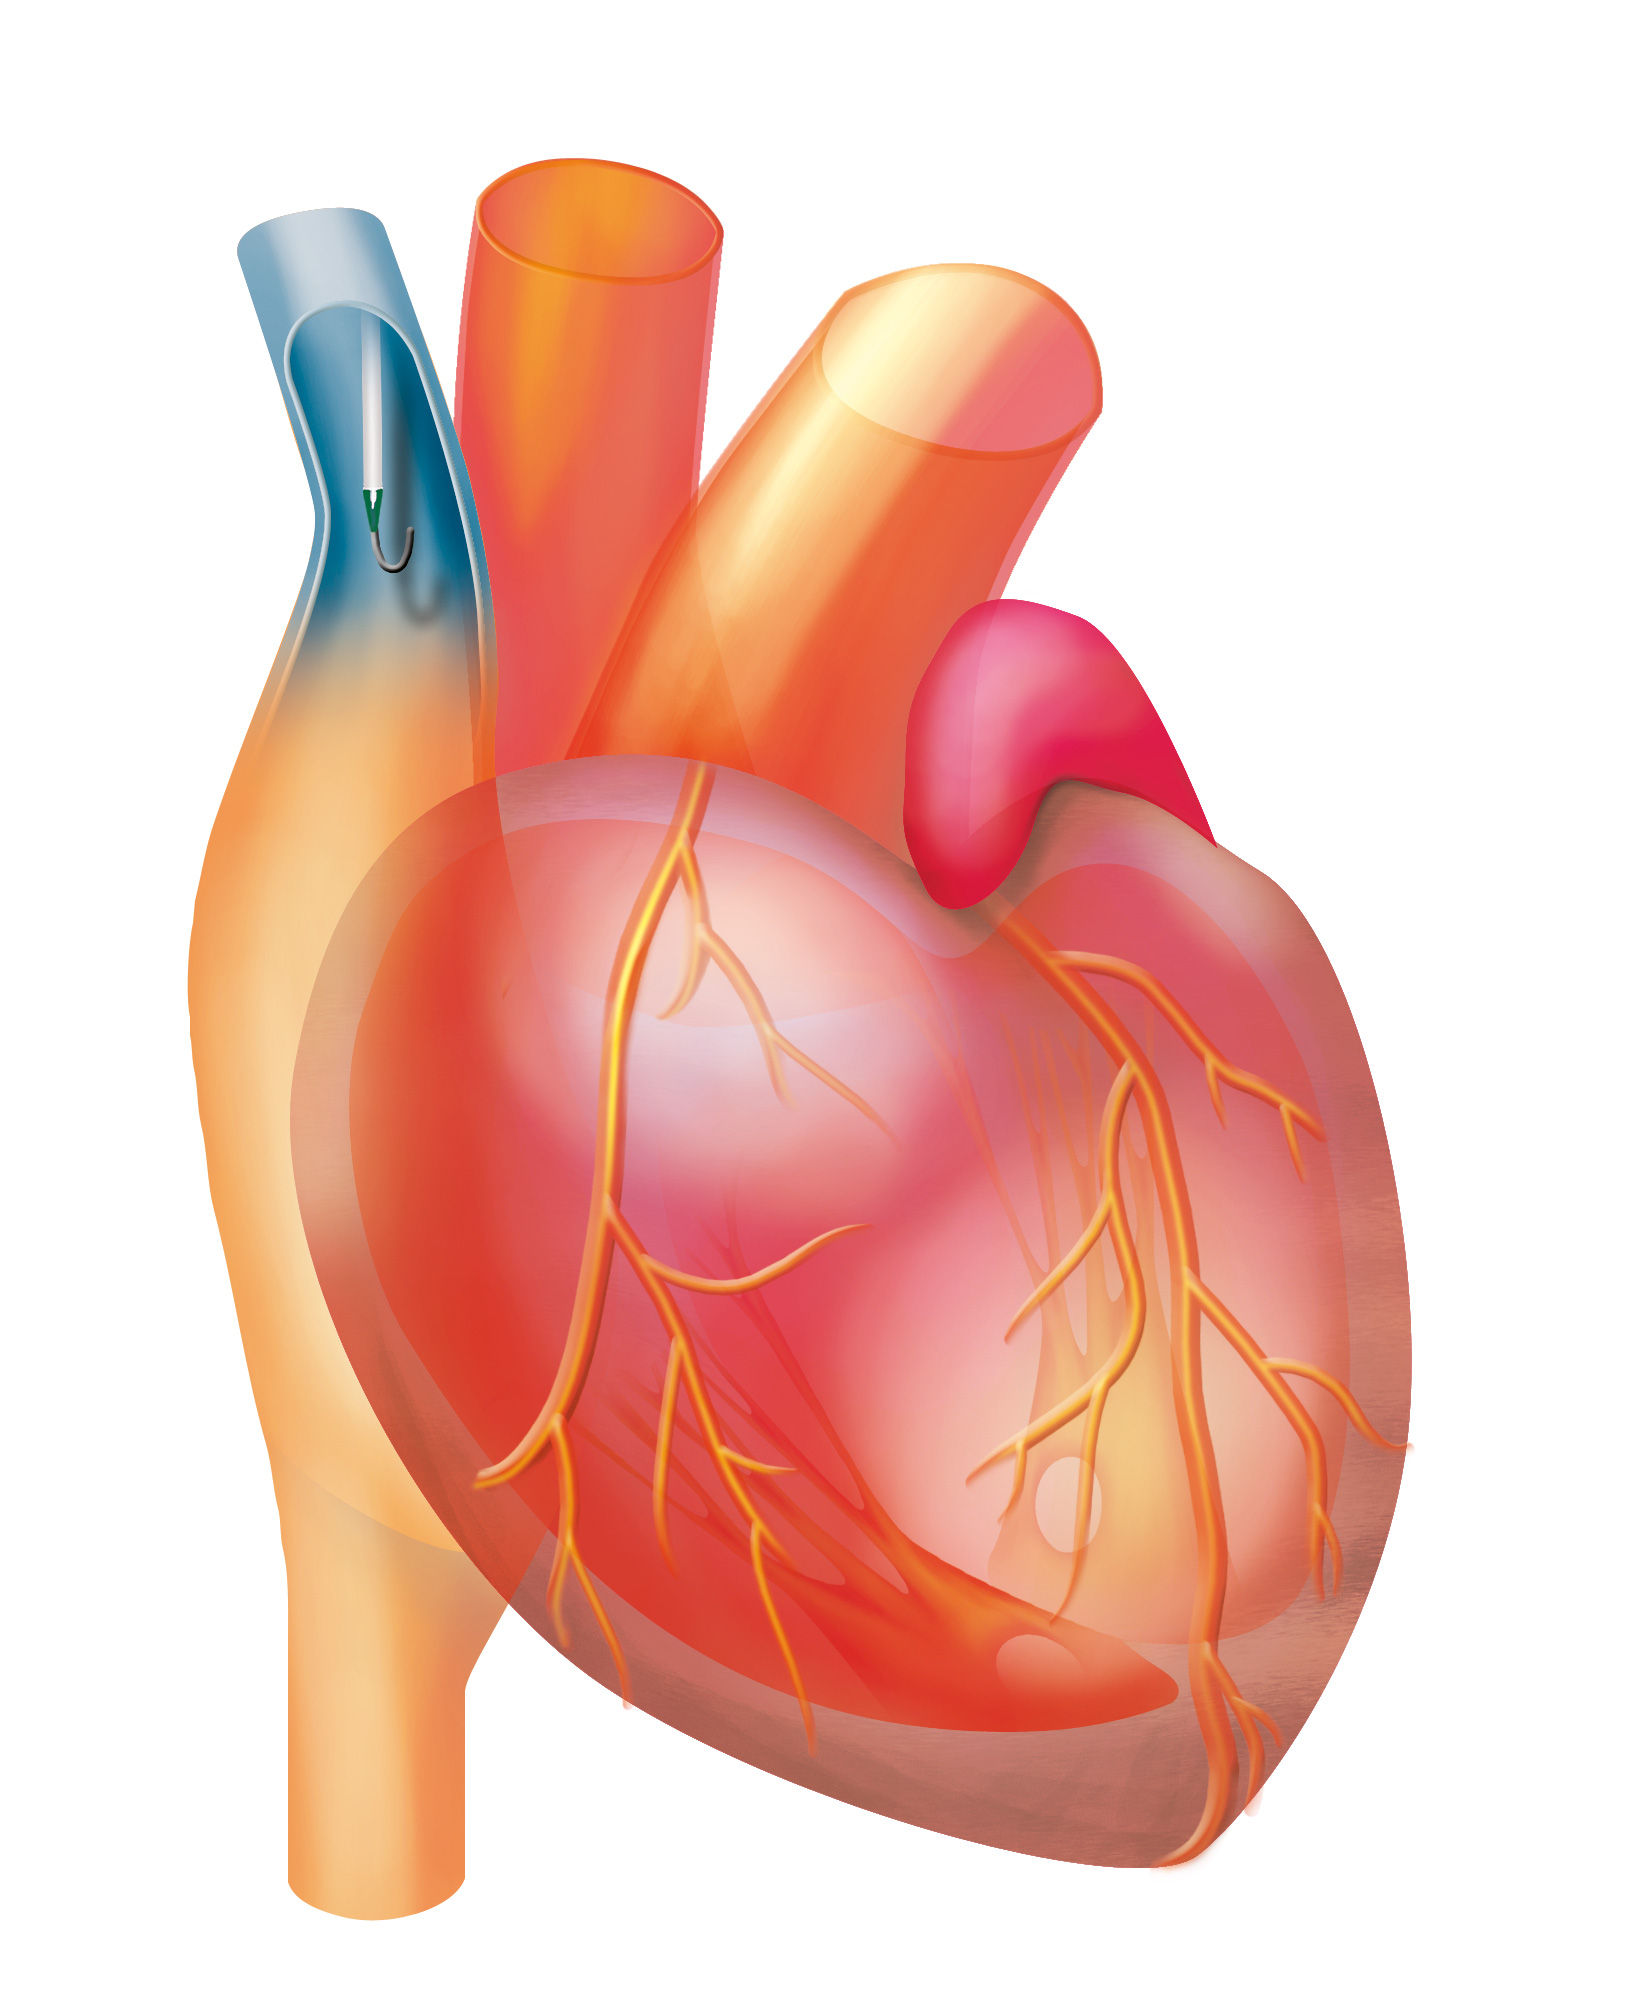

Correct catheter tip positioning6

„ [...] correct position of the catheter has to be ensured during placement"

scheme of catheter tip position Caers J, Fontaine C,Vinh-Hung V et al (2005) Catheter tip position as a risk factor for thrombosis associated with the use of subcutaneous infusion ports. Support Care Cancer 13:325-331​

[H4] Relation between catheter tip position and complication rate [/H4]

[TABLE]

[H4] Location of catheter tip position [/H4]

[H4] Number of patients [/H4]

[H4] Venous thrombosis [/H4]

[H4] Functional problems [/H4]

Brachocephalic vein3245.2%6.5%

SVC cranial 1/34219%16.7%

SVC mid 1/31424.2%1.4%

SVC caudal 1/3661.5%0%

RA or inferior Vena Cava185.5%5.6%

[/TABLE]